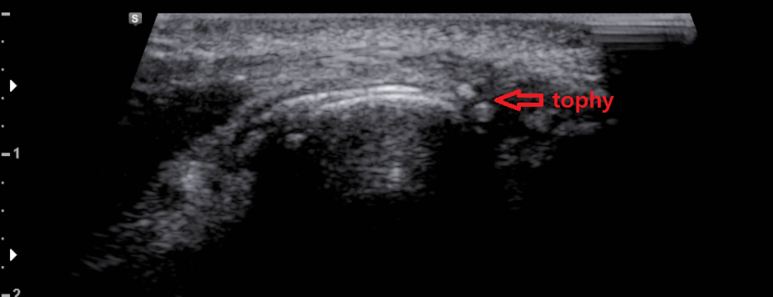

환부 관절의 연골면에 고음영의 요산 침착이 관찰됨 (double contour sign)

관절에 통풍결절이 관찰됨